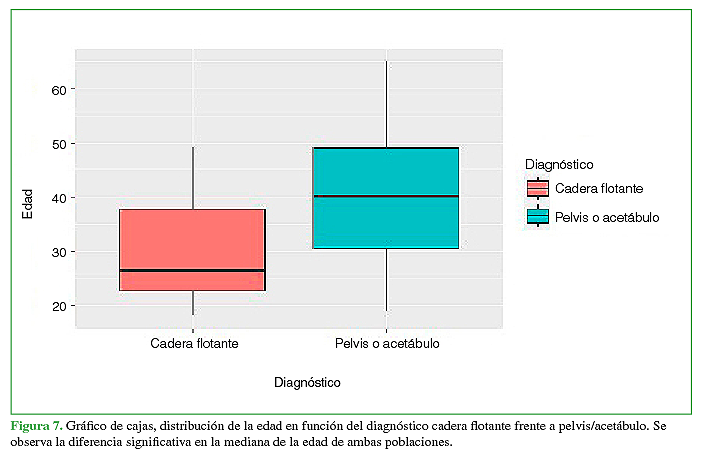

Cuando se compararon ambos grupos, se hallaron diferencias significativas en función de la edad (p <0,0002) (Figura 7). En virtud de esta diferencia, se realizó el emparejamiento de la muestra por las características de edad y sexo, de modo tal que los grupos fueran comparables.